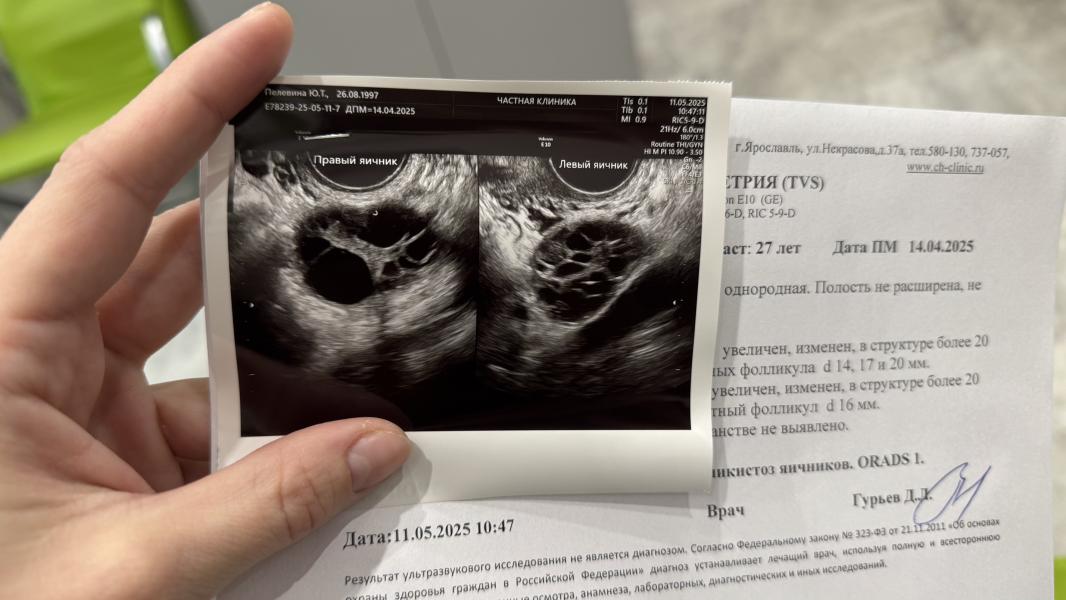

40 фолликулов в каждом яичнике, 3 доминантных справа и 1 слева… У меня всё…

Та картина что была вчера на фолликулометрии - у меня впервые. Всегда было максимальное кол-во фолликул 10 штук в каждом яичнике, а тут больше 40. Но я ходила в лучшую клинику города, где фолликулы считала сама программа. Там мне тоже сказали признаки ановуляции, несмотря на ДФ.

Врач тоже подумал, что я на гормональной стимуляции. Но я не принимала ни раньше ни сейчас ничего абсолютно

Мне сегодня поставили СПКЯ. При мфя фолликулов до 20 штук в обоих суммарно. У меня суммарно 80 🥲